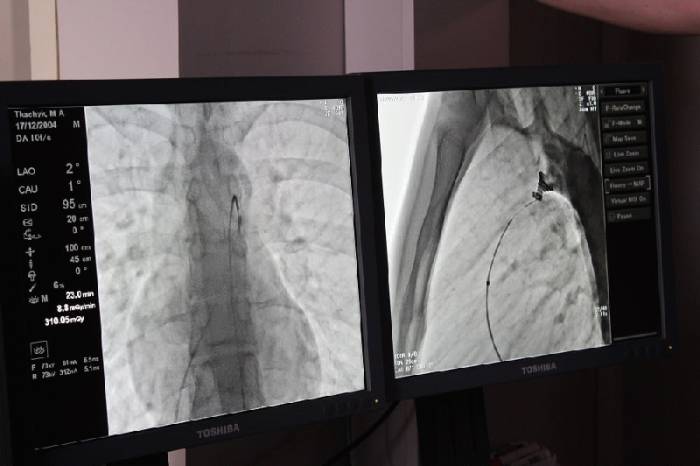

Операція пройшла успішно. Вона була складною і проводилась під рентгенівським контролем із застосуванням ангіографа, під місцевим знечуленням (без наркозу). Через прокол у стегновій вені і артерії в незакриту протоку встановлено оклюдер (маленьку пружинку), яка перекрила потрапляння артеріальної крові у венозне русло.